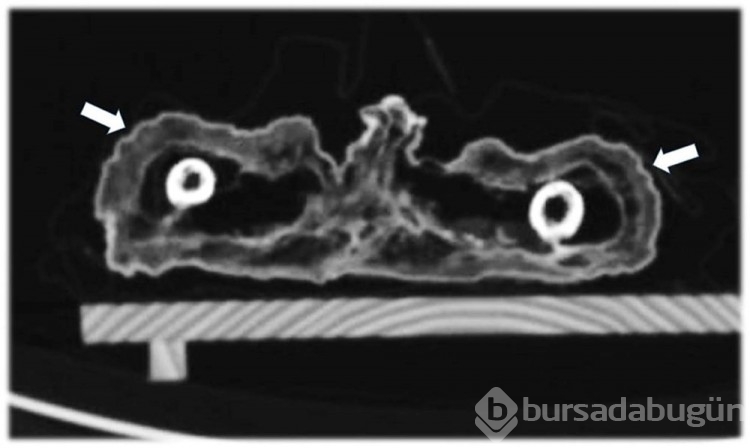

400 yıl önce ölen mumyalanmış bebeğin gizemi çözüldü!

Mumyalanmış bir bebeğin ölüm nedeni, öldükten yaklaşık 400 yıl sonra 'sanal otopsi' sonucunda ortaya çıktı.